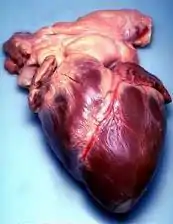

Coração

- presaditev srca: transplante de coração

- zastoj srca: (Medicina) parada cardíaca